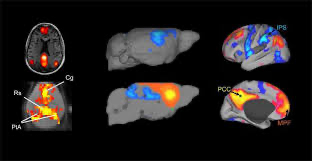

Functional neuroimaging is the use of neuroimaging technology to measure an aspect of brain function, often with a view to understanding the relationship between activity in certain brain areas and specific mental functions.

Functional imaging is the study of human brain function based on analysis of data acquired using brain imaging modalities such as Electroencephalography (EEG), Magnetoencephalography (MEG), functionalMagnetic Resonance Imaging (fMRI), Positron Emission Tomography (PET) or Optical Imaging

Functional Magnetic Resonance imaging (fMRI)

Functional magnetic resonance imaging or functional MRI (fMRI) measures brain activity by detecting changes associated with blood flow. This technique relies on the fact that cerebral blood flow and neuronal activation are coupled. When an area of the brain is in use, blood flow to that region also increases.